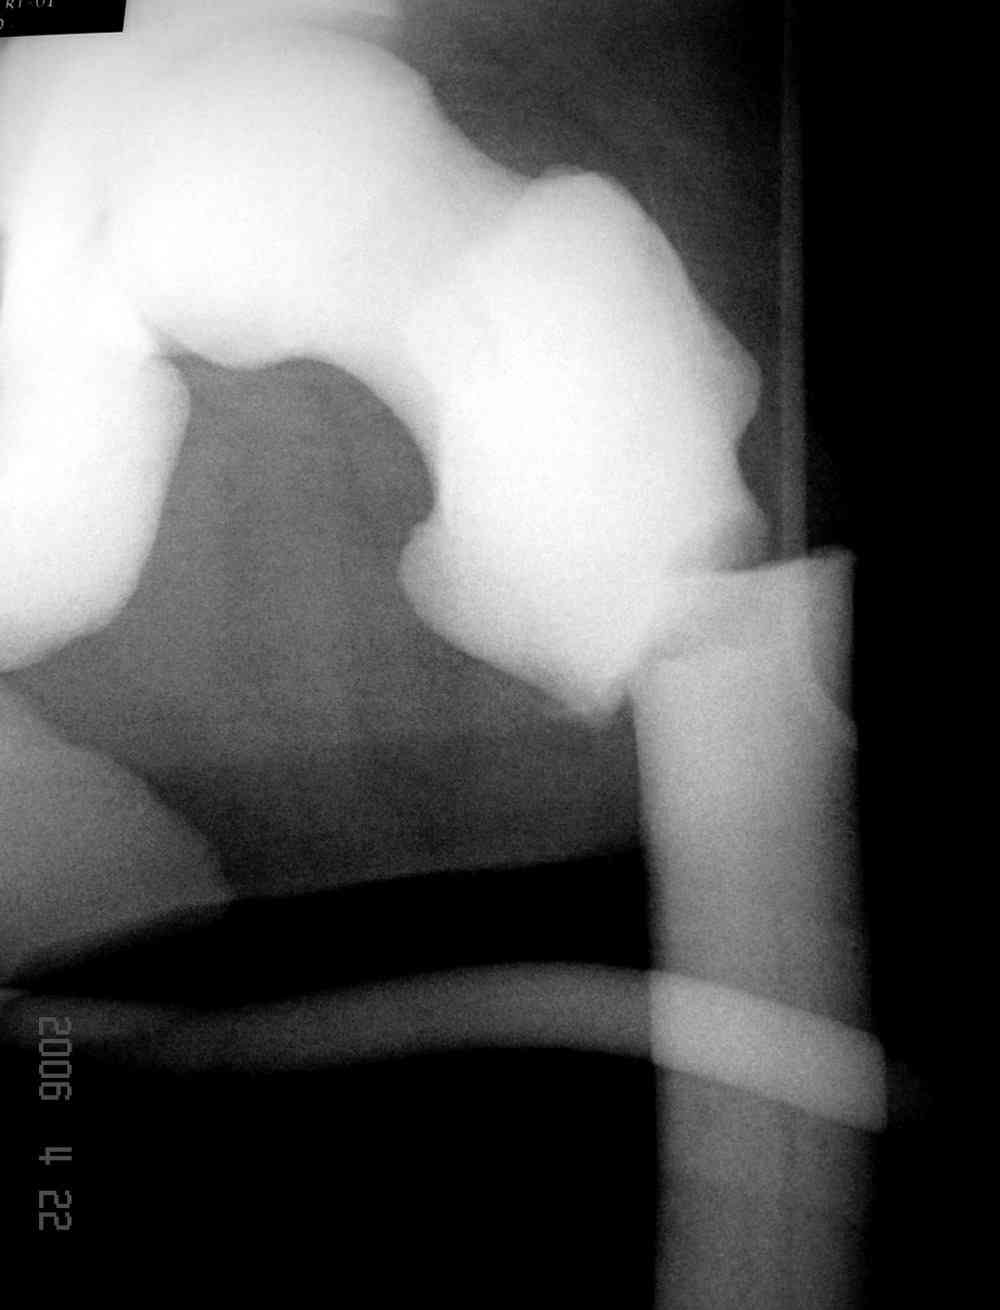

Здесь у меня дополнительные снимки с большим разрешением и в разных режимах, а то те дигитал снимки совсем очень блеклые, может, эти изображени изменят выбор тактики

После неудачной попытки скелетного вытяжения в первом мед.учреждении, после осмотра снимков и изучения истории, поставили диагноз “Остеопетроз” или мраморная болезнь, редкая наследственная костная паталогия, где имеется нарушение формации остеокластов.

Конечно, было бы идеальным применение интрамедуллярного остеосинтеза, но учитывая прежний собственный опыт (лечил перелом бедра) и

публикации, предупреждающие о трудностях при обработке кости (иногда из-за неподготовленности инструментария результатом была неадекватная фиксация перелома, или перенос операции из-за фактора усталости оперирующего персонала), решили применить пластину (и в этом же случае был выбран Synthes plate, так что представитель за два дня

зароботал... на десерт тоже).

Заказаны были дополнительные различные дрели, и на следующий день, усиленной бригадой, больного прооперировали, потратив на каждое отверстие около 25-35 минут, хотя сверлили с охлаждением по нарастающей по диаметру сверл и с их заменой каждые 2 мм сверления.

Теперь стоит задача со сращением перелома, из-за отсутствия литературных данных по применению костных стимуляторов при остеопетрозе, и не зная как поведет в этой среде Grafton, все таки надеюсь, что даст толчок к стимуляцию, решил применить пастообразную деминерализованную костную матрицу, расположив спереди между отломками.